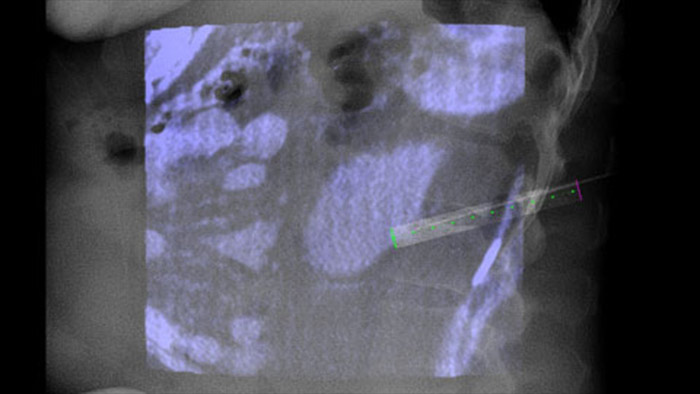

O XperGuide fornece uma orientação de imagem em tempo real altamente precisa de cada agulha para uma posição alvo, sobrepondo trajetórias pré-planeadas com imagiologia fluoroscópica.3